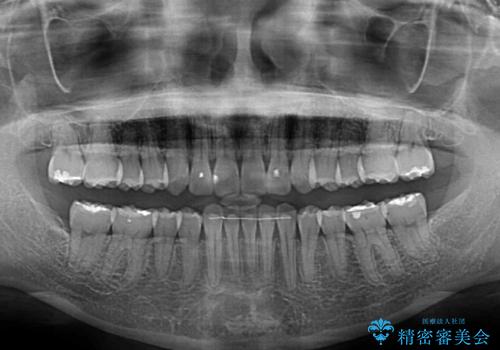

- 捻れた前歯が飛び出しており、口が閉じにくいとのことで来院された患者様です。

出っ歯というわけではないものの、前歯の捻転により口唇が押し出されている状態でした。

親知らずを抜去し、歯列全体を後方に移動させつつ、IPR(歯と歯の間を削る)でスペースを獲得し、インビザラインを用いて叢生を解消しながら前歯の突出を改善することとしました。

骨格的に上下正中がずれていたため、奥歯がしっかりと噛み合うか心配でしたが、ずれているなりに、しっかりとした咬み合わせとなりました。